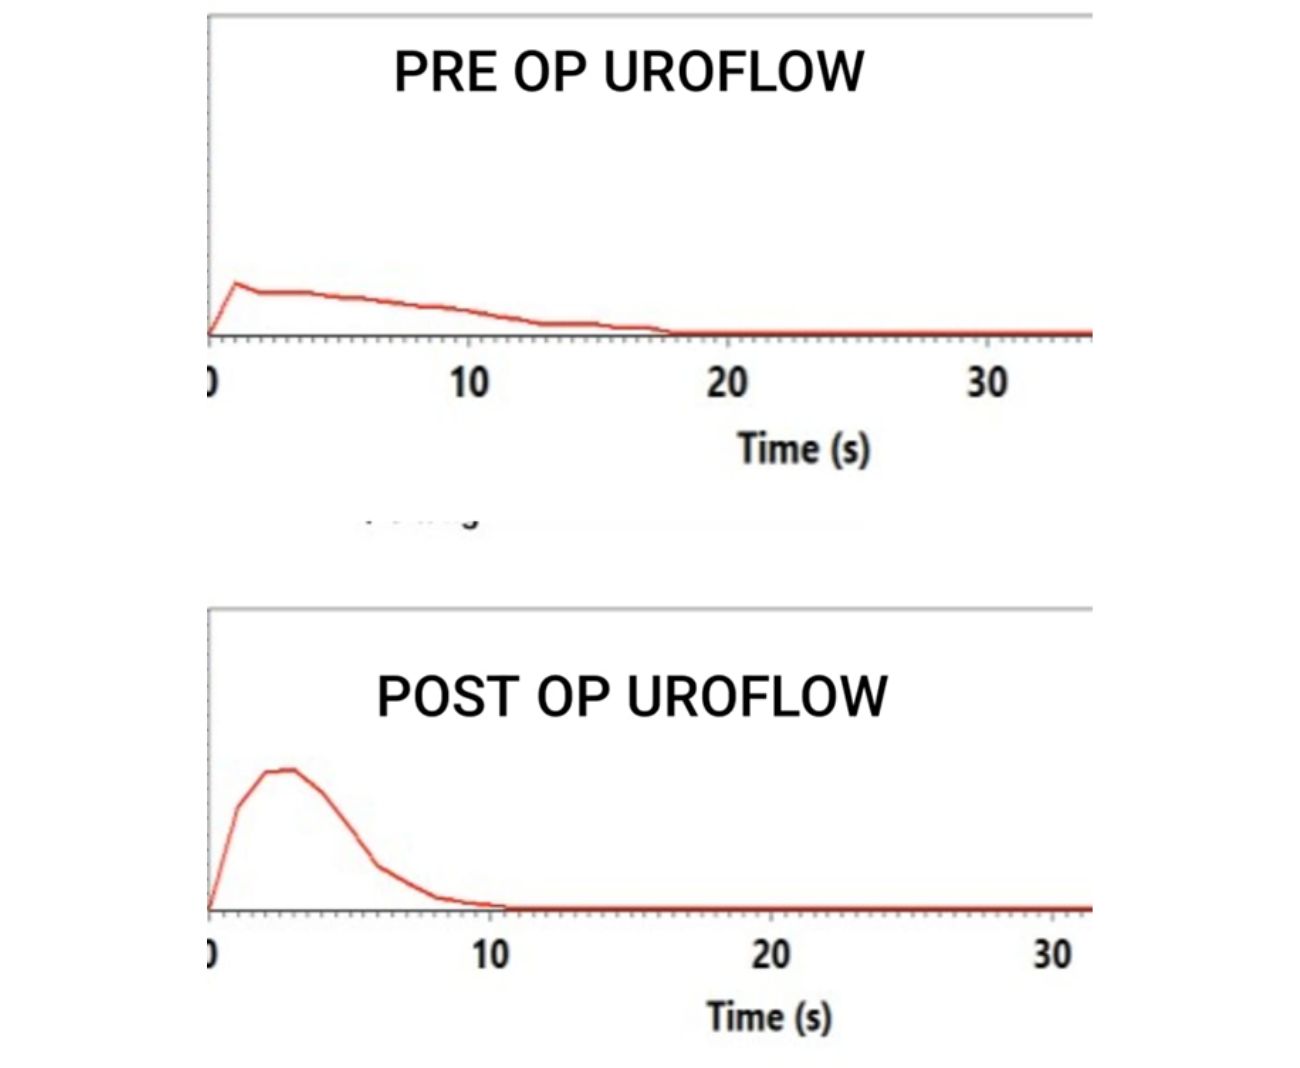

Laparoscopic pyeloplasty is considered the gold-standard treatment for UPJ obstruction (UPJO) because of its excellent outcomes.

👉 Around 90–95% of patients experience long-term relief after Laparoscopic Pyeloplasty.

✅ Restoration of normal urine flow

✅ Reduction in kidney swelling (hydronephrosis)

✅ Relief from pain and recurrent infections

✅ Preservation or improvement of kidney function